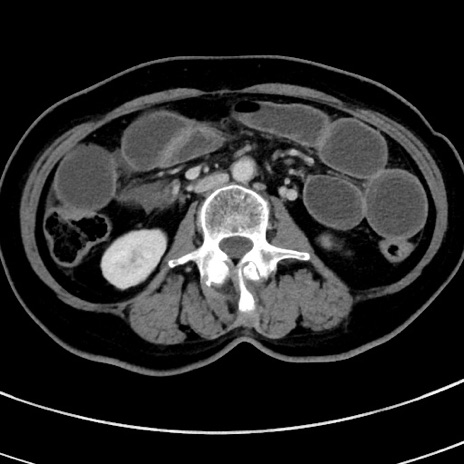

症例9(横断像)

【症例】 60歳代女性

【主訴】むかつき、みぞおちの痛み

【現病歴】3日前よりむかつきがあり、食事がとれない。

【既往歴】糖尿病

【身体所見】発熱なし、心窩部圧痛軽度あるも、腹膜刺激症状なし。

【データ】WBC 7400、CRP 1.92